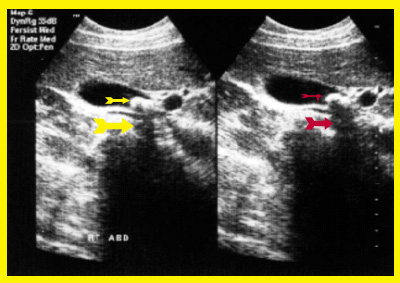

- בדיקת אולטרה-סאונד של כיס המרה (תצלום 1.8).

בדיקת האולטרה-סאונד היא מכשיר עזר חשוב באבחון הלוקים באבנים בכיס המרה, בצהבת או במצבים דלקתיים חריפים. אמינות הבדיקה היא גבוהה - 95%. בבדיקה זו מודגמות האבנים בכיס המרה כנקודות בהירות שמאחוריהן "צל אקוסטי" (Acoustic shadow) - אזור בלא החזרת קול (האבן חוסמת את הקול) (תצלום 1.8). אם הנבדק משנה תנוחה, האבן זזה, והדבר מודגם בבדיקה. אבנים בדרכי המרה ניתנות להדגמה ב- 20% מהמקרים. דרכי מרה מורחבות אפשר להדגים בלוקים בחסימה בדרכי המרה. בחולים אלה ההרחבה יכולה להיות של דרכי המרה החוץ ו\או התוך-כבדיות. (תצלום 2.8 ו- 3.8). נוזל סביב כיס המרה ודופן מעובה של כיס המרה מעידים על דלקת של כיס המרה (תצלום 4.8). אפשר לבצע בדיקת אולטרה-סאונד של דרכי המרה בזמן הניתוח ולאתר אבנים בדרכי המרה.